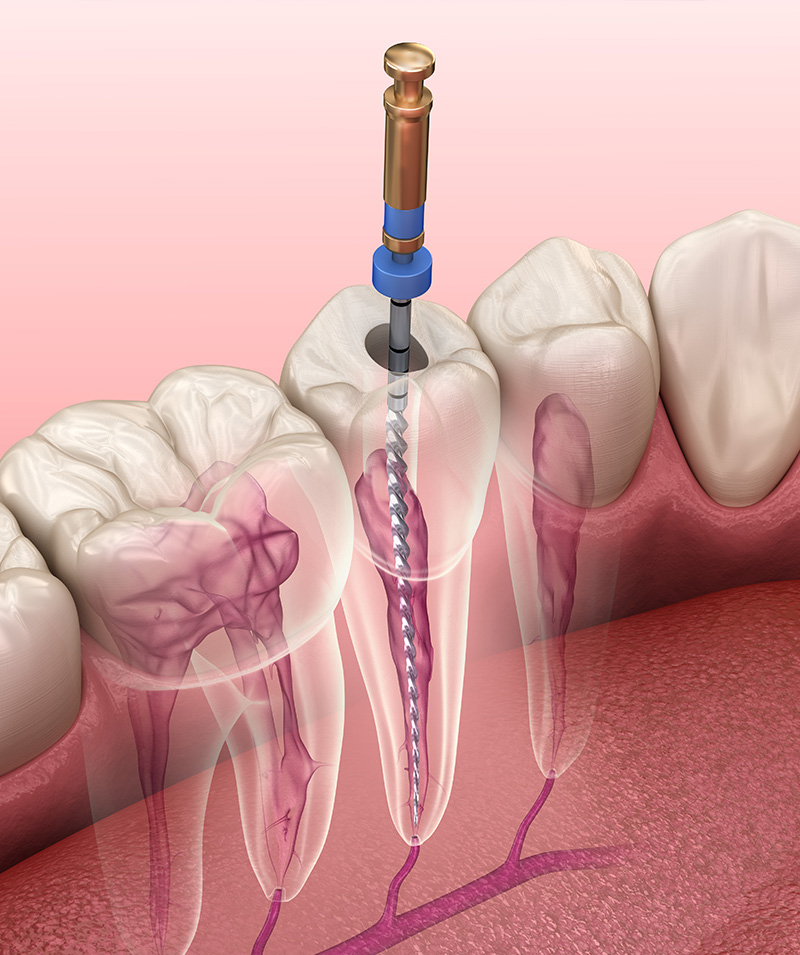

マイクロスコープ(歯科用顕微鏡)

マイクロスコープは治療部位を最大で20倍にまで拡大して観察できる、いわば「歯の治療に特化した高性能な手術用顕微鏡」です。 肉眼では到底確認することのできない、歯の根の内部の微細な構造や詰め物・被せ物と歯との間に存在するミクロン単位のわずかな隙間、あるいは歯の表面にできた微細な亀裂などを、明るい照明下で鮮明に映し出します。 これにより、診断の精度を高めるとともに、より精密で確実な治療を可能にします。

「再発を防ぐ」ための精密根管治療

根管治療の長期的な成功は、細菌に感染した神経組織をいかに徹底的に、そして確実に取り残しなく除去できるかにかかっています。 マイクロスコープを用いることで、髪の毛よりも細く複雑に走行することもある根管の内部構造を見逃すことなく、隅々まで精密に清掃・消毒することが可能となります。 これにより、治療後の根の病気の再発リスクを大幅に低減し、歯そのものの寿命を延ばすことに大きく貢献します。